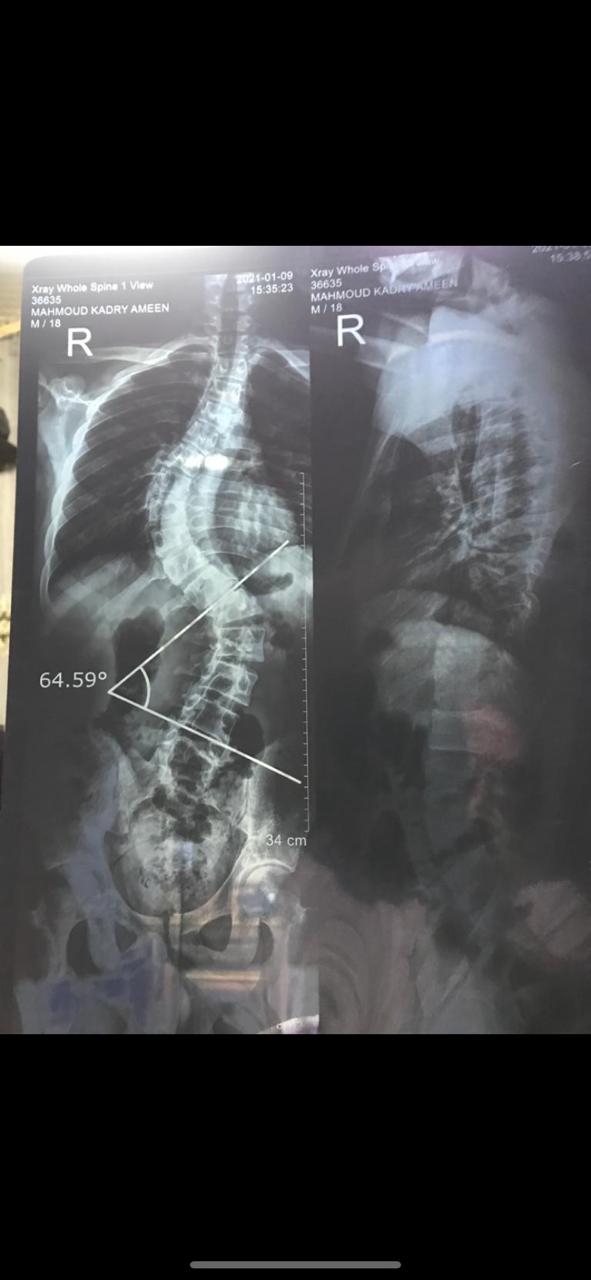

وأوضحت الهيئة أن المريض، يبلغ من العمر 20 عامًا، وكان يعاني من عدم القدرة على الحركة، وأن الفحوصات الطبية أظهرت إصابته بإعوجاج حاد وتشوهات في العمود الفقري بدرجة كبيرة مصاحب بأعراض مرضية، مشيرة إلى أنه تم إجراء العملية للمريض بنجاح واستقرار حالته الصحية.